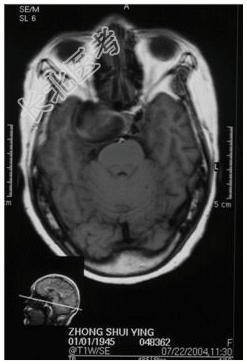

- [材料题] 患者,女性,59岁,因复视、右面瘫及蚁行感半年,间有头疼,无呕吐入院。体检:神清,右外展不全,复视,右面部皮肤感觉尚好,伸舌居中,右指鼻试验(-),四肢(-)。做头颅MRI检查。

- 简答题1、请问诊断是什么?

- 简答题2、诊断依据是什么?

- 简答题3、鉴别诊断有哪些?